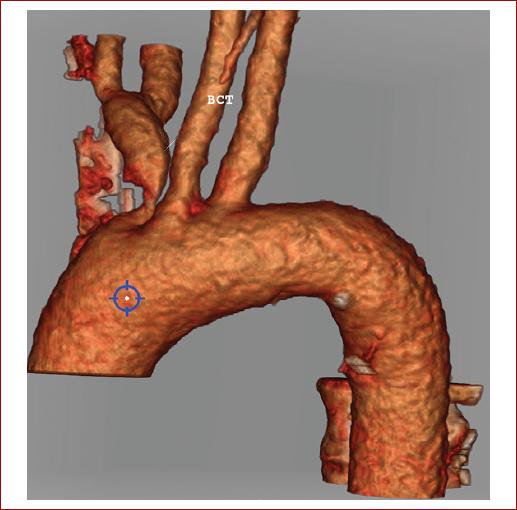

Se realiza una ecografía de troncos supraaórticos (TSA), en la cual se objetivan pequeñas placas de ateroma en ambos bulbos carotídeos. En el eje carotídeo derecho se evidencia un flujo atenuado con ascenso sistólico lento y velocidad pico sistólica disminuida. La arteria vertebral derecha muestra una velocidad pico sistólica elevada, con ausencia de flujo diastólico y morfología de inversión de flujo en diástole en relación con la actividad del miembro superior derecho. Se realiza una angiotomografía de TSA que muestra ateromatosis calcificada en segmentos petrosos de ambas arterias carótidas internas (Fig. 1) y estenosis de aproximadamente 8 mm de longitud del origen del TBC con una reducción de diámetro superior al 90%, y con dilatación posestenótica, como puede observarse en la reconstrucción 3D de las imágenes tomográficas (Fig. 2). En la resonancia magnética cerebral se aprecian lesiones sugestivas de eventos isquémicos previos en el lóbulo frontal derecho distal correspondientes a territorios de la arteria cerebral anterior y la arteria cerebral media derecha (Fig. 3), por lo que se ingresa al paciente en la unidad de ictus.

Figura 2 Reconstrucción 3D en la que se observa la estenosis del tronco braquiocefálico y la dilatación posestenótica.